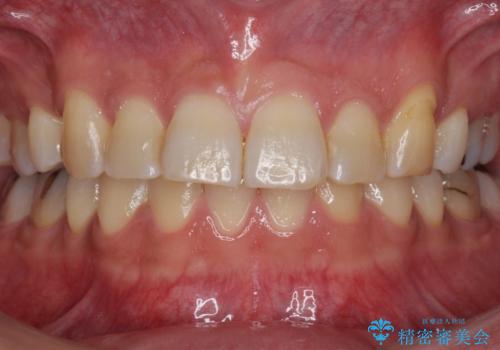

[インビザライン] 前歯のガタつき・すれ違い マウスピース矯正治療